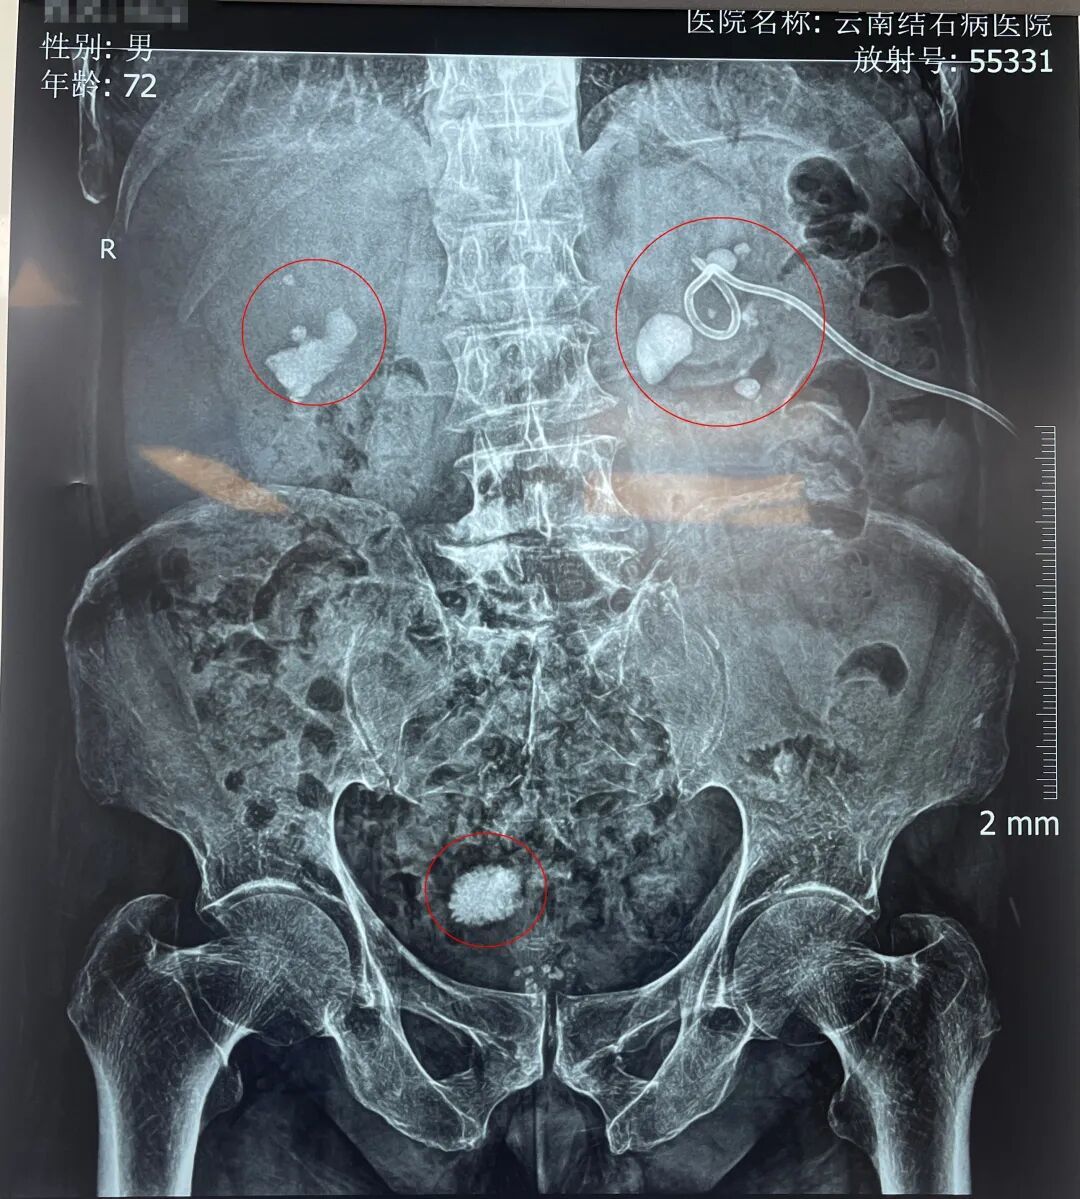

入院后,黄鸿宾主任为周爷爷安排了全面系统的检查。结果显示,其身体状况犹如一座年久失修的老屋,多处功能受损:前列腺增生伴钙化、膀胱结石、双肾多发性结石伴积水、脂肪肝、高血压等。

周爷爷的检查片子

可谓“牵一发而动全身”,面对如此复杂的临床状况,黄鸿宾主任为其量身定制了个体化治疗方案,即采用“瑞梦”前列腺热蒸汽消融术+膀胱镜下碎石取石术+纤维软性肾镜碎石取石术。一次手术,解决了他前列腺增生、膀胱结石、双肾结石等多重病痛。